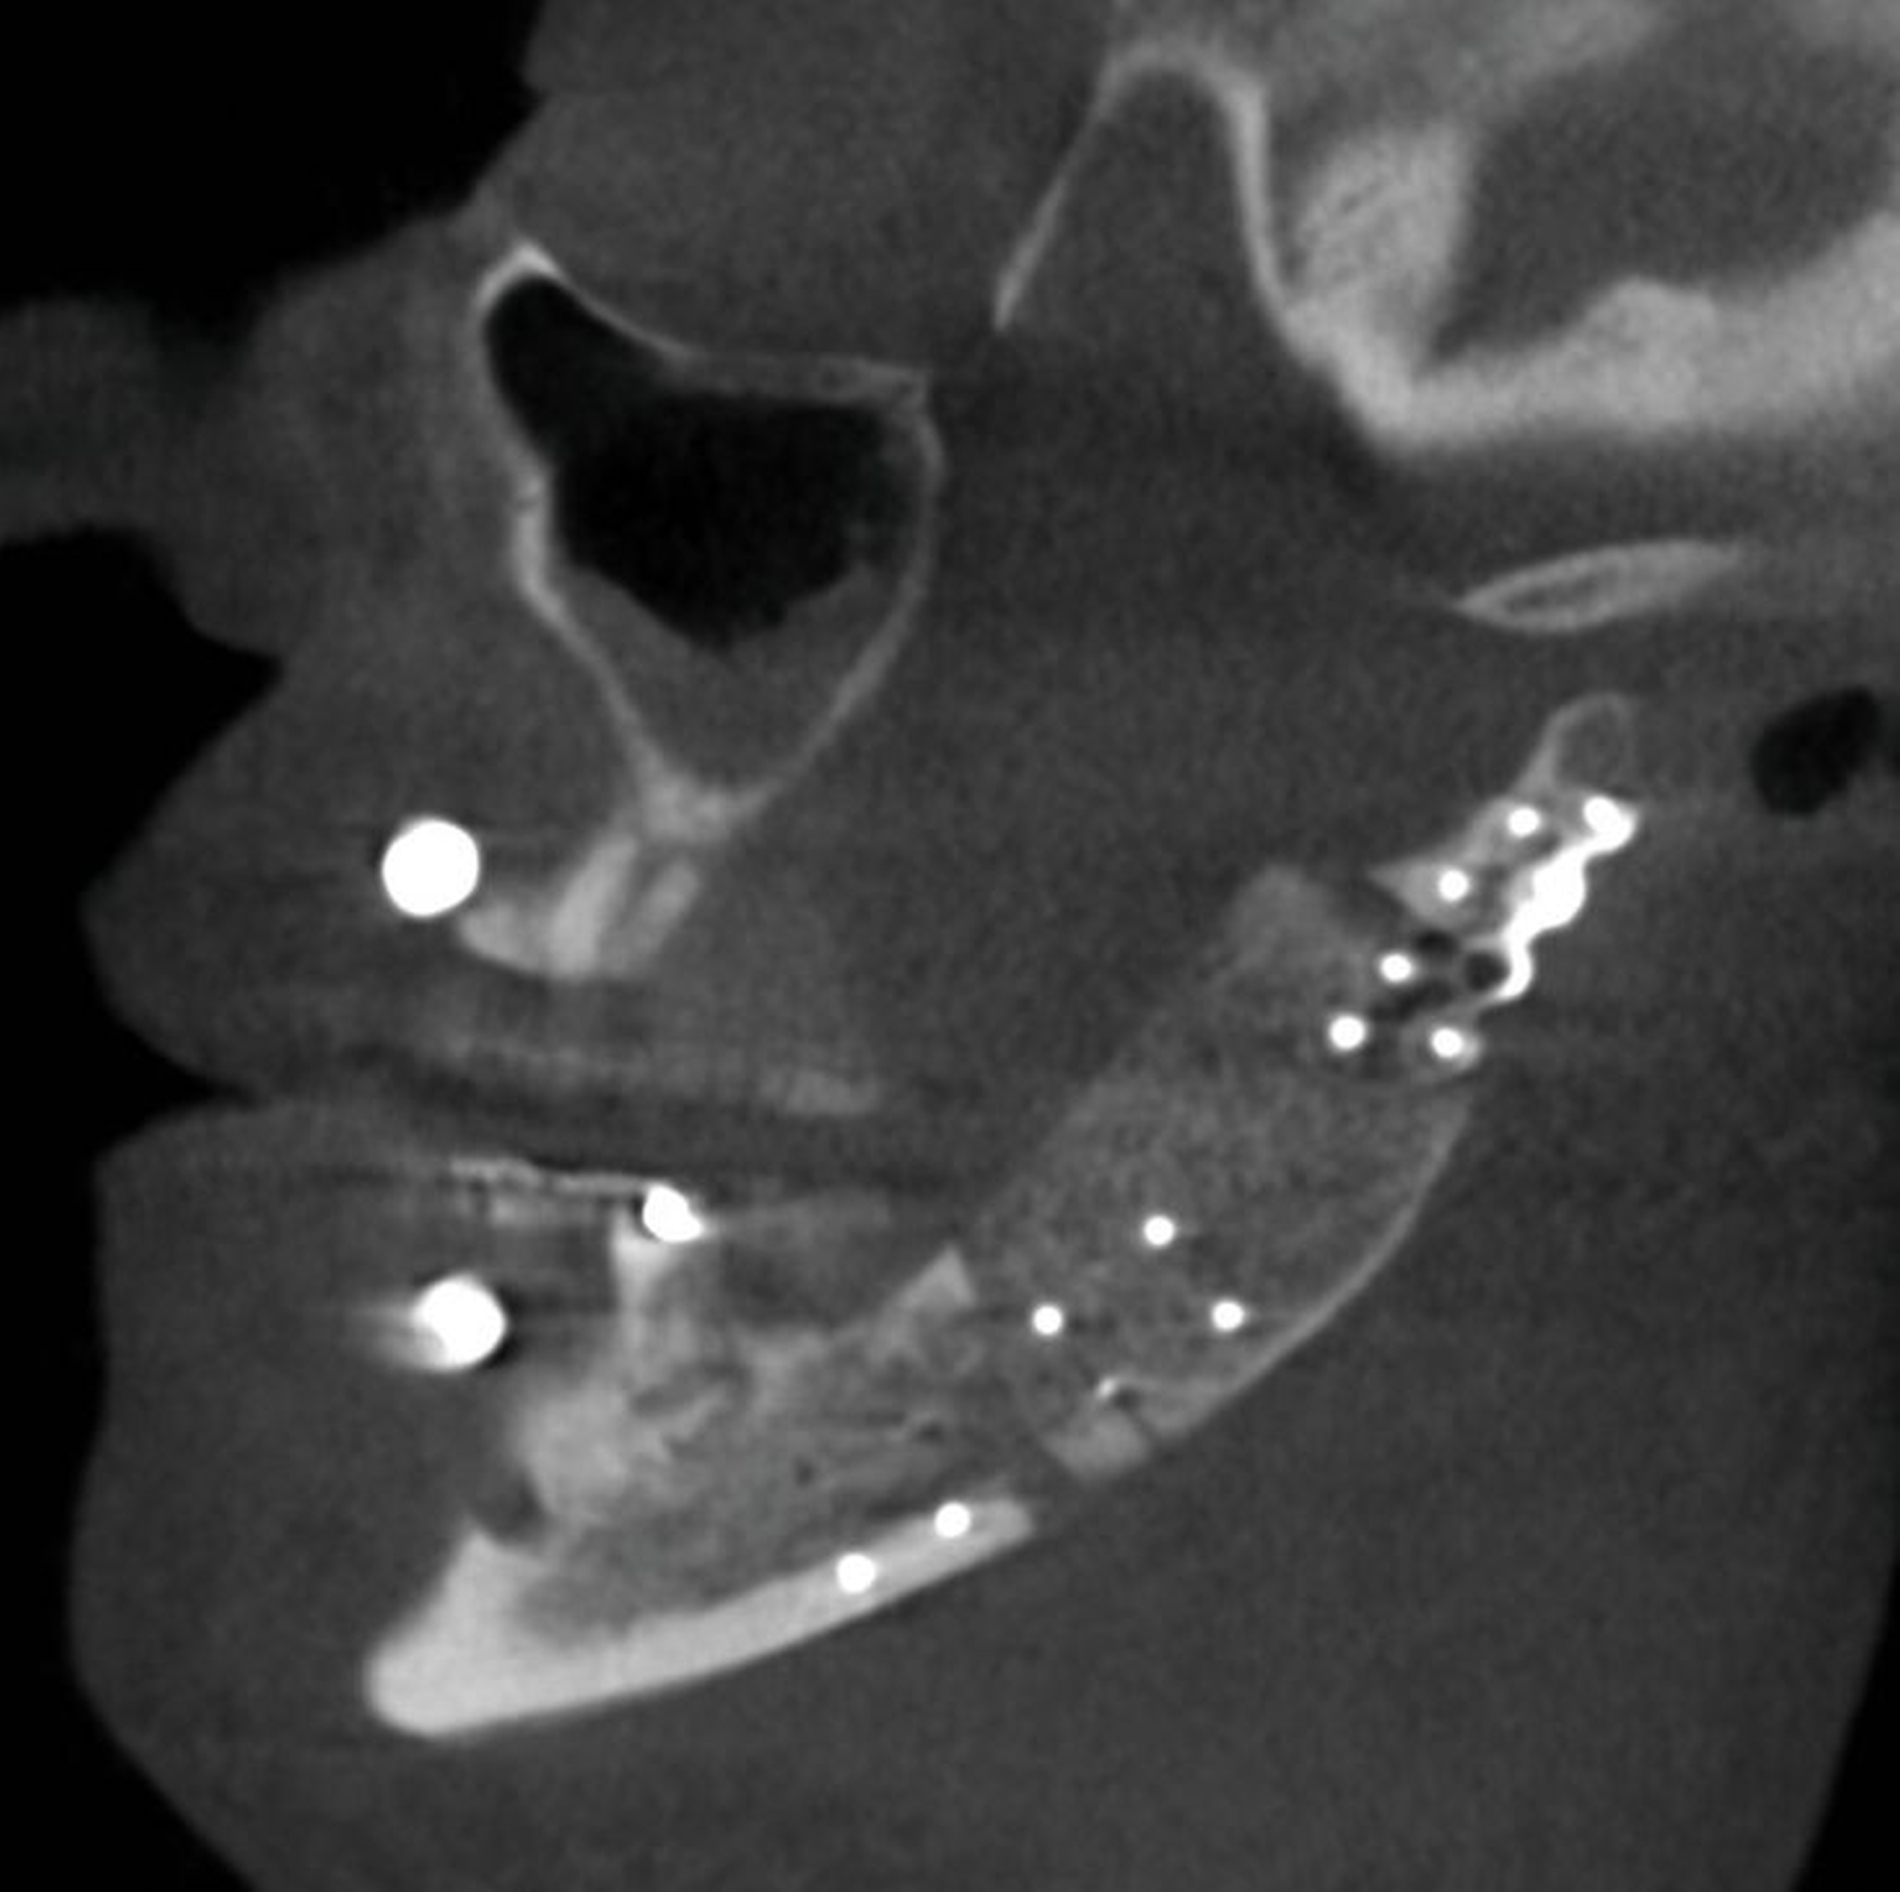

Aktuell befindet sich die Patientin im Rahmen der Tumornachsorge im engmaschigen klinischen Recall. Aufgrund der geringen Tumorgröße und nicht nachweisbarer lymphatischer Metastasierung konnte auf eine adjuvante Bestrahlung verzichtet werden. Die kürzlich erfolgte 12-Monats-CT-Kontrolle nach Therapie zeigte ein regelhaftes Ergebnis ohne Nachweis eines Lokalrezidivs oder pathologisch vergrößerter Lymphknoten (Abbildungen 4 und 5).